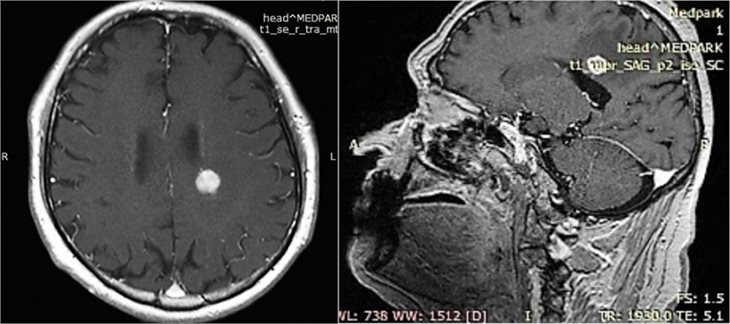

На днях, команда хирургов Medpark, возглавляемая нейрохирургом Адрианом Дану, удалила опухоль диаметром 1,5 см, расположенную в лобной доле, на глубине 5-6 см.

Операция была крайне сложной с технической точки зрения, поскольку опухоль развилась вблизи центров, отвечающих за речь и движение в правой руке и ноге. Несмотря на это, было принято решение срочно удалить это новообразование, пока оно не повредило здоровую часть мозга.

Интраоперационное использование УЗИ внесло существенный вклад в успех вмешательства и стало результатом продуктивного сотрудничества между командами нейрохирургов и сонологов.